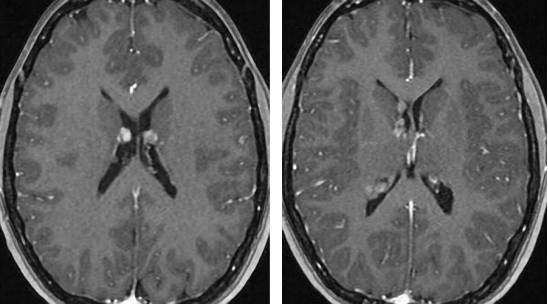

图1. 胶样囊肿一般无明显强化,T1相表现为等信号。T2加权图像上,则表现为较白质更强的信号影,外周一圈低信号环。

图2. 颅咽管瘤在MR图像上表现为不均匀的囊性和实质性信号(上图)。其囊性成分在T1相上表现为高信号,结节部分则表现为不均匀的显著强化(左下图)。CT上表现为点状钙化(右下图)。